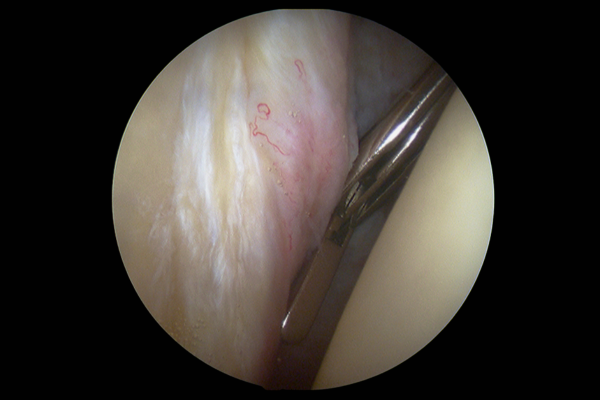

img

Arthroscopic Surgery